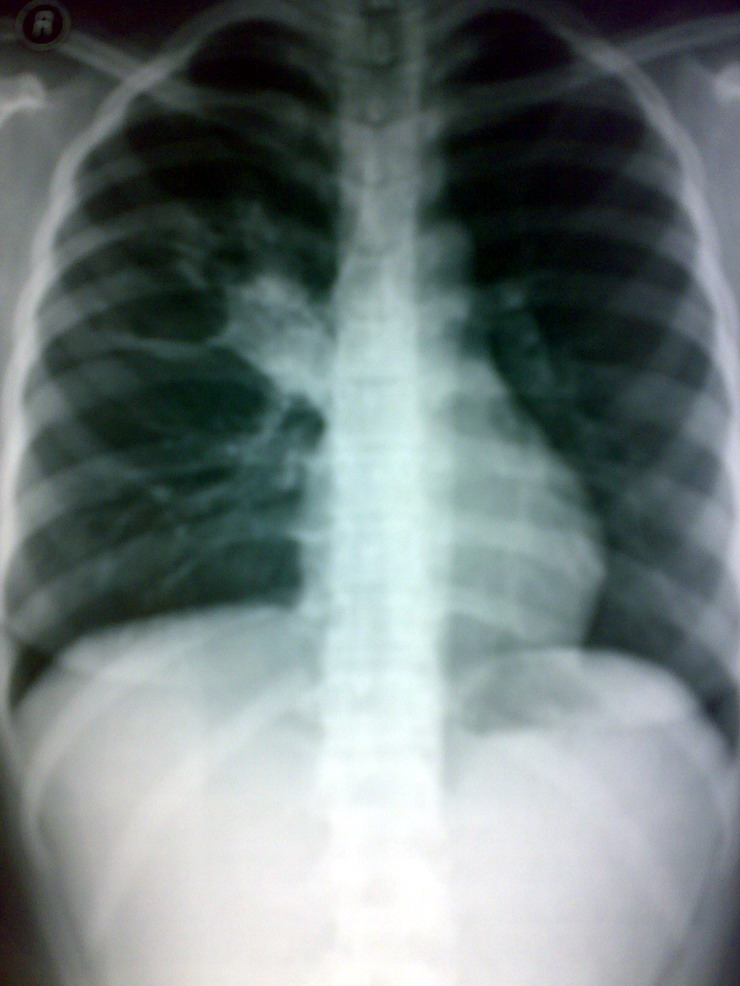

标题: X3774:女 35岁 咳痰两周 低热 [打印本页]

右肺门淋巴tb

肺结核可能性大,建议作进一步检查。

右肺结核可能性大。建议:行ct扫描检查。

右肺结核可能性大,建议ct检查。